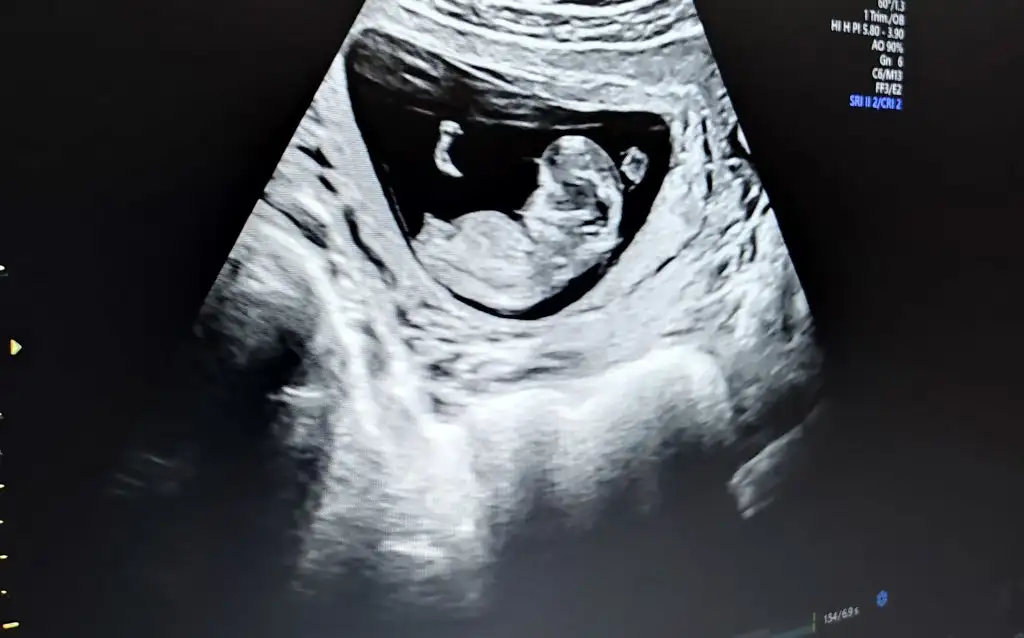

dr soylemeden siz gorun genital nub teorisi ( bebegin cinsiyeti)

Canım bizede 12+5 de tahminde bulunurmusun karından usd dr bir tahminde bulundu ama net değil dedi🤗

• image.webp

image.webp

16 KB · Görüntüleme: 63